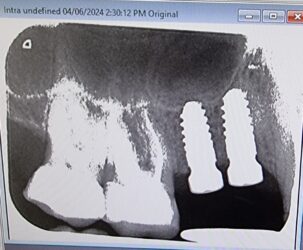

Hi nice to meet you guys. I am new to implant crowns and just wanted your opinion. I have a case for the 14 15 for impressions this Tuesday. I noticed on the radiographs there is quite a bit of bone loss on the 14 two months after placement. I do intend to take another xray on the day but is this cause for concern or is it normal. Thanks

View more comments-

Is it just me or can we sort of see a slight preview of the future bone loss in the first x ray?

The answer to your question is that yes, it is a cause for concern, but also that yes this is normal. It does happen to us all.

Best thing to do now is stop the progression of the bone loss. Curious to hear what you guys would do.

-

I think at this stage your best ally is going to be thick connective tissue and a well polished (not glazed) crown with good profile. It is a concern, but not enough to remove the implant. I have actually seen some cases fill in later if the crown, hygiene and tissue is ideal.